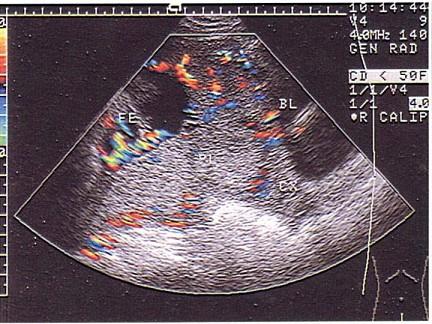

问题 女性,25岁,停经33周。阴道无痛性出血2天。B超检查如图,最可能的诊断为?(?)

选项 A.中央性前置胎盘 B.胎盘早期剥离 C.胎儿脐带绕颈 D.胎儿畸形 E.边缘性前置胎盘

答案 A